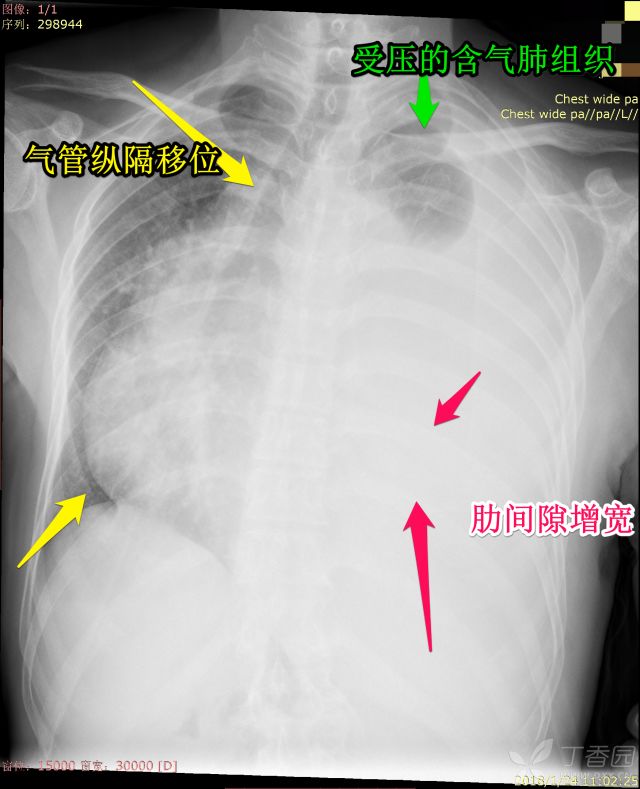

之前我们分享了秒懂胸片!扒一扒胸片的基础知识(可点击查看),那这一次就老生常谈,先发一波病例走起,病例很简单,都是白肺,各位来诊断吧。备选一共有:上叶肺不张、全肺不张、胸腔积液、大叶性肺炎

3.全叶肺不张